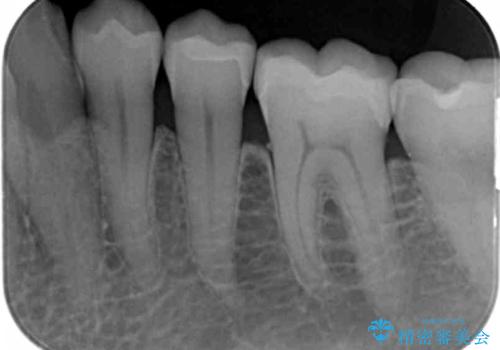

- 長年見た目が気になっていた銀歯のやりかえを希望されて来院されました。

銀歯を丁寧に除去し、セラミクインレーによる置き換えを行いました。

セラミックインレーの治療に際しては、拡大鏡を用いた丁寧な除去・形成、シリコン印象材による精密な型取りを行い、虫歯の再発を防ぐような精密修復を実践していきます。

自然なセラミクの仕上がりに満足いただくことができました。